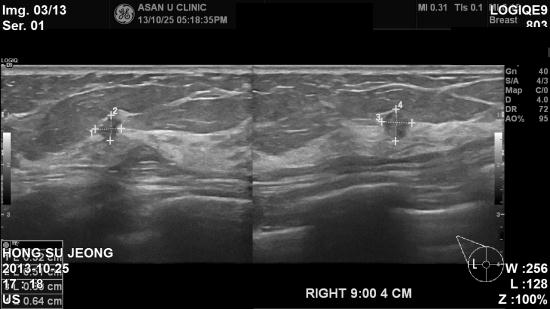

초음파검사에서 우측유방에

0.6cm 혹이 있어 조직검사를 시행하였으며,

침윤성 유방암으로

진단되었습니다.